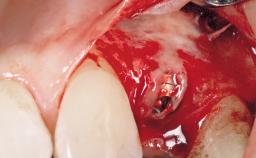

Late Flapless Placement of an Implant in a Maxillary Left Central Incisor Site

A 39-year-old male patient presented with a chief complaint of discomfort and gingival discoloration around his maxillary left central incisor. He was in good general health and was a non-smoker. His past dental history was significant because of the traumatic fracture of tooth 21 in a sporting accident at age 13. Initial dental treatment included endodontic therapy and a full-coverage restoration. The patient became symptomatic 5 years later, when structural failure of the tooth resulted in the dislodgment of the crown. Endodontic retreatment, apical surgery, and post-and-core restoration were performed.

Type of Implants One-Piece

Bone Volume Deficient horizontally, requiring prior grafting